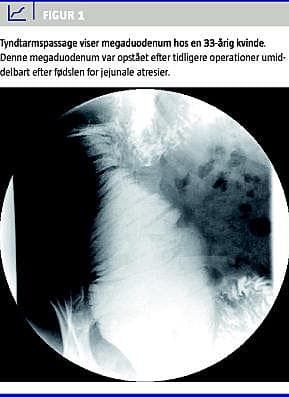

Anoskopi, analfysiologiske undersøgelser og blodprøver var normale. Colontransittiden (CTT) [2] var forlænget (76 timer), hvilket fandtes at være i overensstemmelse med patientens kroniske obstipation. De røntgenfaste markører befandt sig alle i venstre side af abdomen. Ultralyd og computertomografi af abdomen viste en luftfyldt struktur i højre side. Røntgen af colon viste, at alle colonslynger lå til venstre for columna, men derudover fandtes der ingen patologi. Der blev foretaget tarmpassage, som viste udtalt dilatation af duodenums andet og tredje stykke (Figur 1 ). Dette blev genfundet ved duodenoskopi, hvor der fandtes retention og voldsom dilatation af duodenum.